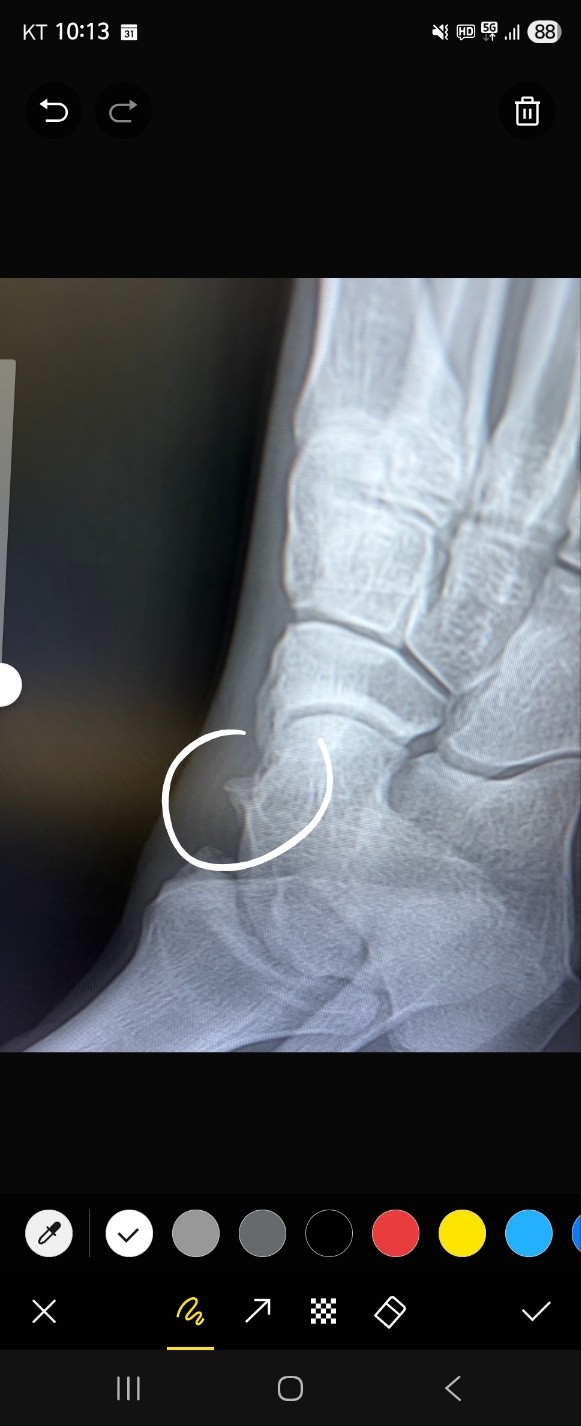

임현우원장 발목 뼈가 자라서 통증이 점점 심해지는데 수술이 필요할까요 ?

안녕하세요. 발목 통증이 점점 심해지는거 같아 문의 남깁니다.

통증이 시작된지는 꽤 오랜시간이 지났구요, 일주일에 두번정도 운동(농구)는 꾸준히 하고 있습니다.

운동을 할때와 하고 나서 발목 안쪽을 찌르는듯한 통증이 계속 되고 발목의 피로감이 더해지는거 같습니다.

X-ray 사진(사진은 2년전쯤)을 첨부했는데, 어떤 증상인건지, 수술이 필요하다면

수술 및 입원 기간은 어떻게 되고 재활여부도 알려주시면 감사하겠습니다.